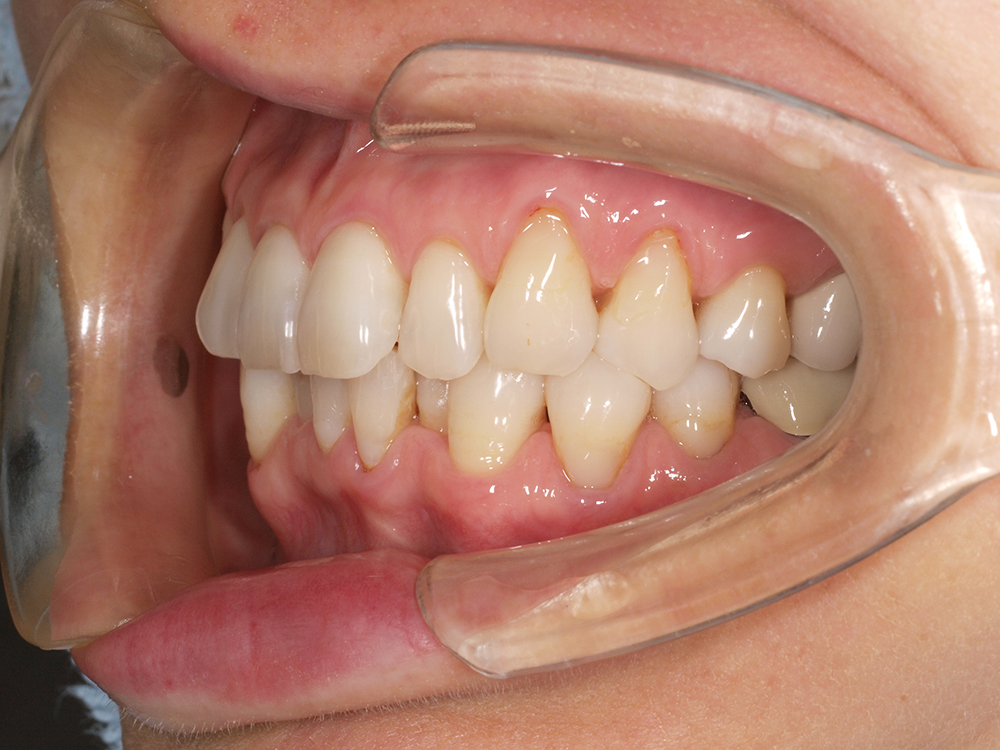

53歳 男性

- 主訴

- 全然噛めない。上の歯が取れてきた

- 処置内容

- 上顎:8本 下顎:2本

- 治療費用

- 上顎:約320万円(税込)、下顎:約160万円(税込)

- 治療期間

-

上顎:1年(仮歯まで8か月)

下顎:8か月(仮歯まで5か月)

- リスク

- 上部構造物、仮歯の破折、術後の腫れ(3日)、人工歯根脱落リスクがあります